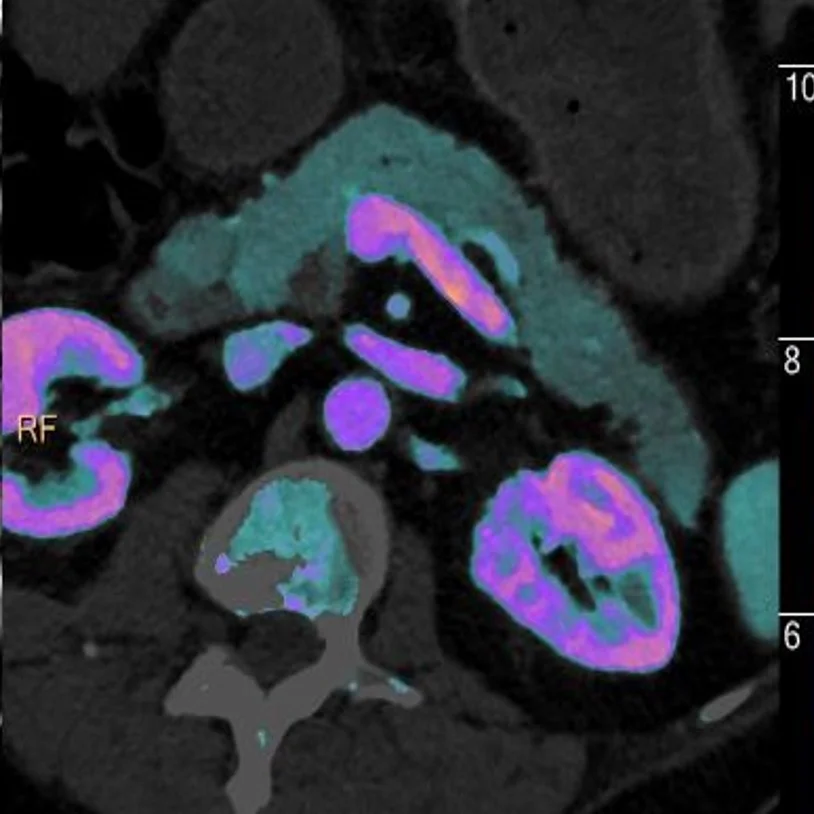

Iodine map, axial oblique: Lesion is easy to see! Hypoenhancement is characteristic of pancreatic adenocarcinomas.